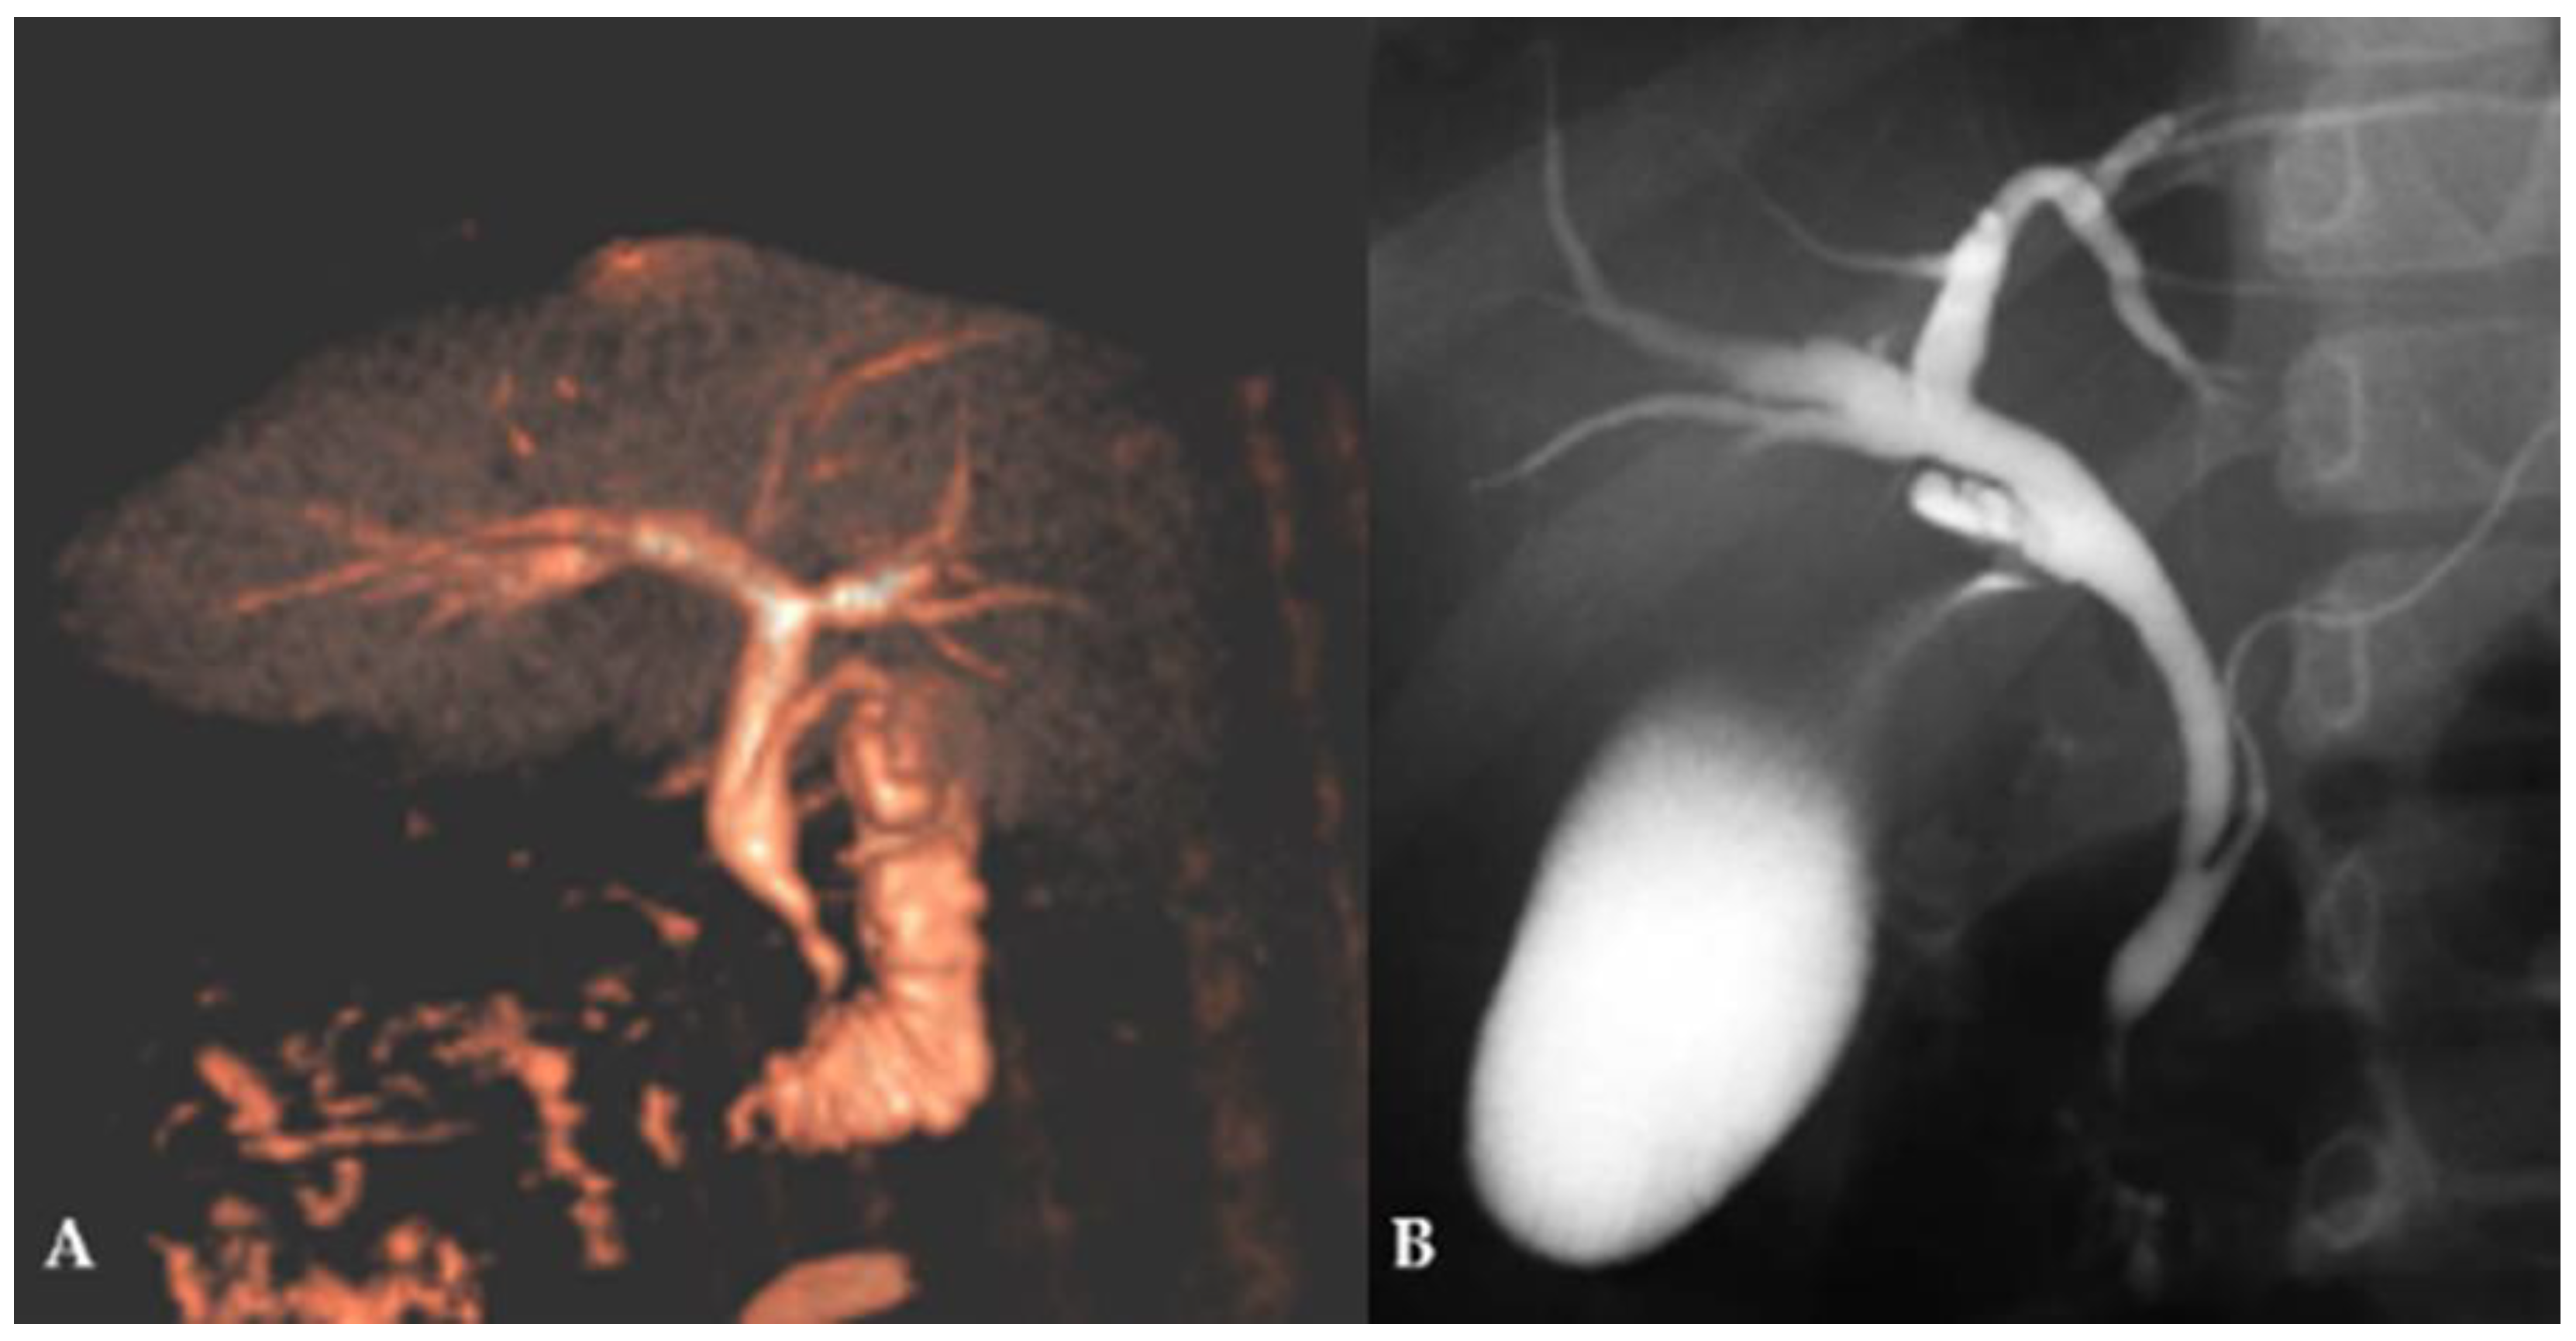

After confirmation of CBD dilatation, MRCP (Figure 2A) and, in selected cases, ERCP (Figure 2B) were performed depending on the clinical presentation.

Figure 2. Diagnostic procedure in patient with suspected FFCC: (A)—MRCP in an 8-year-old girl, showing a dilated CBD with a diameter of 6.7 mm and an anomalous pancreaticobiliary junction; (B)—ERCP in a 12-year-old girl, showing a dilated CBD with a diameter of 8 mm and an anomalous pancreaticobiliary junction.